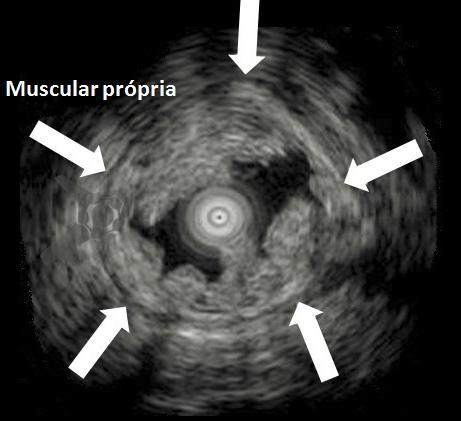

O segredo é um fenômeno chamado redução gravitacional. Ao encher o cólon com água em vez de ar, a flutuabilidade faz a lesão “boiar” para longe da muscular própria, permitindo que a alça capture tecido submucoso adequado sem risco de envolvimento muscular ou perfuração.

Figura 1: Ecoendoscopia evidenciado a mucosa e submucosa ‘flutuando” enquanto a camada muscular se mantém estável. Na UEMR, as lesões flutuam na água por redução gravitacional, permitindo ressecção segura sem envolver a camada muscular.